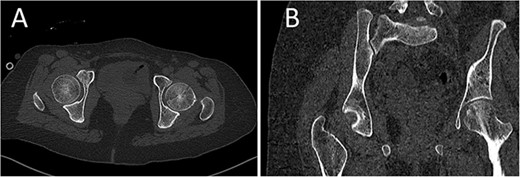

A medically free 42-year female presented to our institute as a life-saving case from a different hospital as she was a victim of unrestrained road traffic accident 2 days prior to presentation. Upon assessment in the emergency department (ER), she was conscious and oriented, and was found to have bilateral lung contusion, and multiple fractures of ribs. She also had a left sided vertical femoral head fracture dislocation comprising around 40% of the femoral head (Fig. 1). Closed reduction under conscious sedation was done in the ER, which was successful based on post-reduction imaging studies (Fig. 2). Her chest injuries were treated with chest tube and observation for 10 days. During that time, discussion was made with the patient regarding her situation and conservative management was chosen by way of bed rest and continuation of skeletal traction for 4 weeks with serial radiographs in the hospital on a weekly basis after clearance of her chest injuries. Skeletal traction was discontinued and she was advised to continue bed to wheelchair mobilization for an additional 2 weeks. After 6-weeks from the injury, a Computed Tomography (CT) was done to the patient and revealed signs of fracture healing (Fig. 3). At 3-years after the injury, she was found to have full painless range of motion of the affected hip and has resumed her activity of daily living without any complaints and the images showed a symmetrical joint space of the hips (Fig. 4).

CT scan of the chest, abdomen, and pelvis showing axial (A) and coronal (B) cuts of a left sided Pipkin I fracture comprising large surface of the femoral head with posterior hip dislocation.